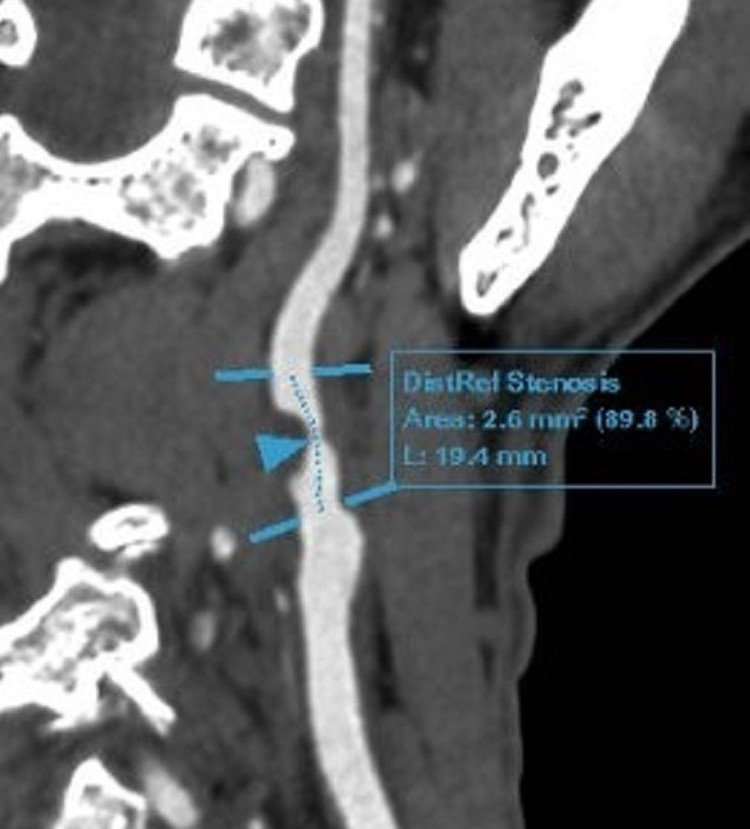

Ông Đ được bác sĩ chỉ định thực hiện xét nghiệm và các kỹ thuật chẩn đoán hình ảnh chuyên sâu tìm nguyên nhân gây đau đầu. Sau đó, ông được chẩn đoán mắc bệnh động mạch cảnh do xơ vữa, hẹp nặng 90% động mạch cảnh trong bên phải, lóc tách nhỏ gốc động mạch cảnh trong bên trái; Bệnh động mạch vành mạn tính; Rối loạn lipid máu.

“Trường hợp của ông Đ đã hút thuốc lá gần 30 năm (tương đương hơn 6.000 bao), đi khám vì các cơn đau đầu nhẹ thoáng qua nhưng đã phát hiện mảng xơ vữa gây hẹp 90% gốc động mạch trong phải, lóc tách nhỏ gốc động mạch cảnh trong. Đây là minh chứng rõ ràng cho tác động nghiêm trọng và âm thầm của thuốc lá lên hệ mạch máu não và tim mạch. Bên cạnh đó, khi thấy các dấu hiệu không rõ ràng như: Chóng mặt, buồn nôn, yếu liệt tay chân hay rối loạn ý thức, người bệnh vẫn tiềm ẩn nguy cơ cao bị đột quỵ nếu không được phát hiện và can thiệp kịp thời”, BS Nam nhấn mạnh.

Phim chụp tổn thương của bệnh nhân. Ảnh CAND